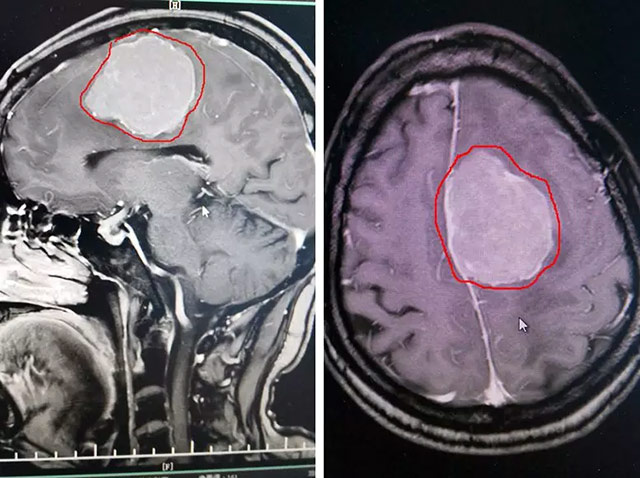

经检查,患者有明显右侧肢体乏力、精细运动差,并有思维迟缓、语言迟缓、记忆力下降等症状。头颅MR增强显示,患者左侧大脑镰旁有巨大团块状异常信号,肿瘤大小约5公分,如鸡蛋大小。该肿瘤巨大,压迫症状明显,周围水肿。且有继续增大的趋向,导致颅内压进一步升高,形成脑疝,有危及生命的可能。

▲ 患者颅内脑膜瘤如鸡蛋大小,可能危及生命